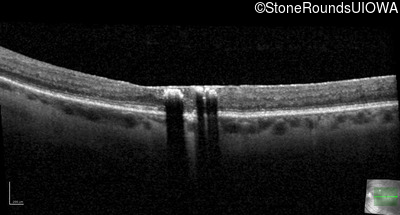

Age at visit: 47 years

OD OS

This 47 year old woman began wearing glasses at age 5 and had cataract surgery at age 32. At that time her doctor noticed a retinal abnormality.